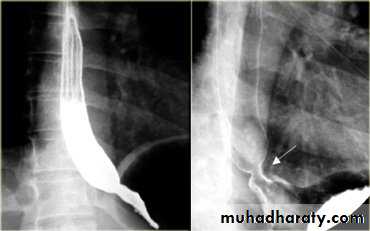

LEFT: Dilated esophagus (arrows) appears as long, well-defined structure paralleling heart RIGHT: Dilated esophagus usually deviates to right. Narrowing (arrow) at hiatus.

LEFT: CT shows dilated esophagus (arrow) that led to esophagram.RIGHT: Esophagram shows narrowing (arrow) at level of hiatus.